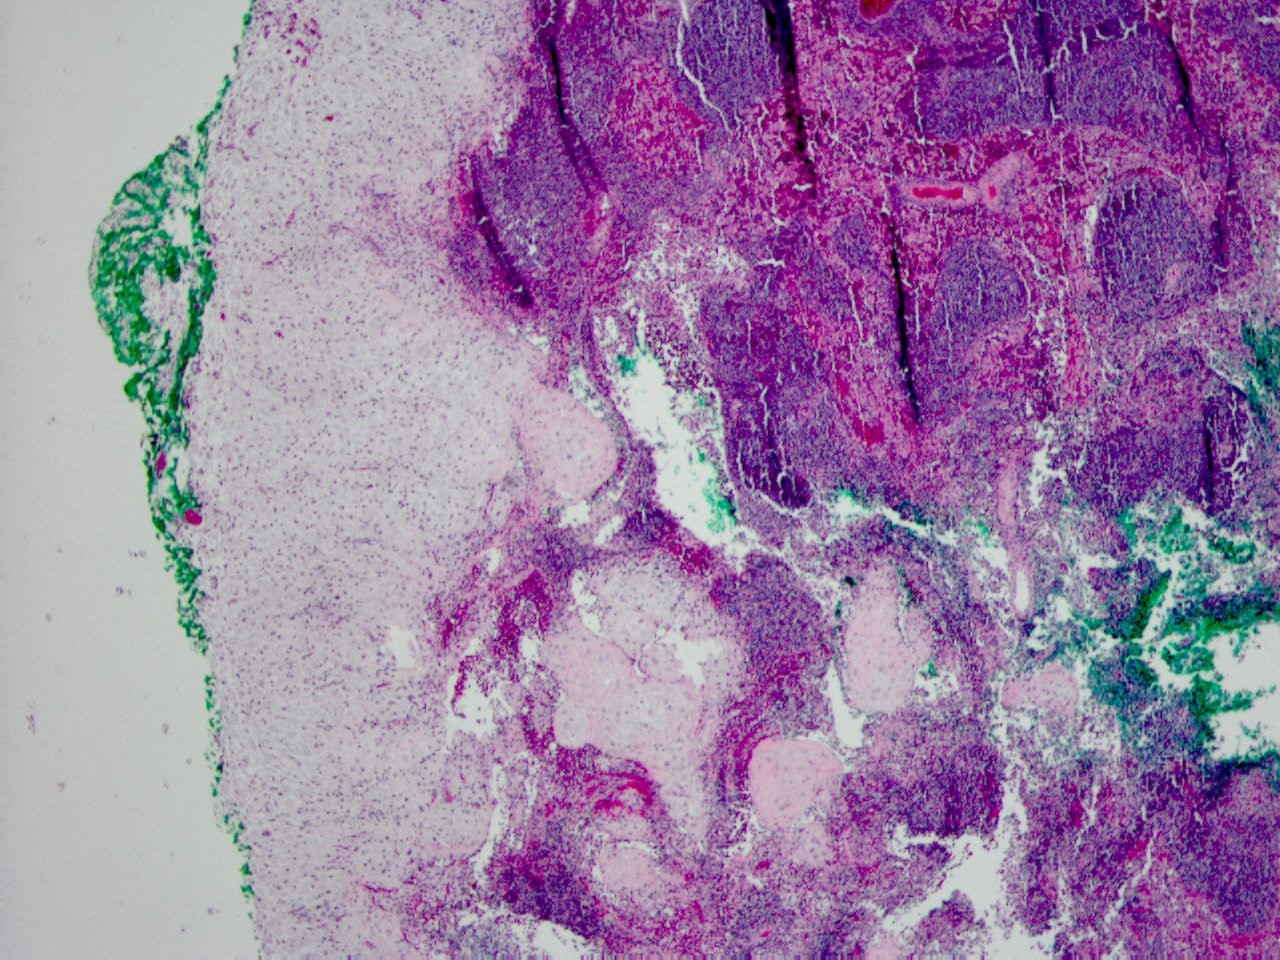

40 year old female with pelvic mass and friable cervix, biopsy was performed at OSH....

Clinical History